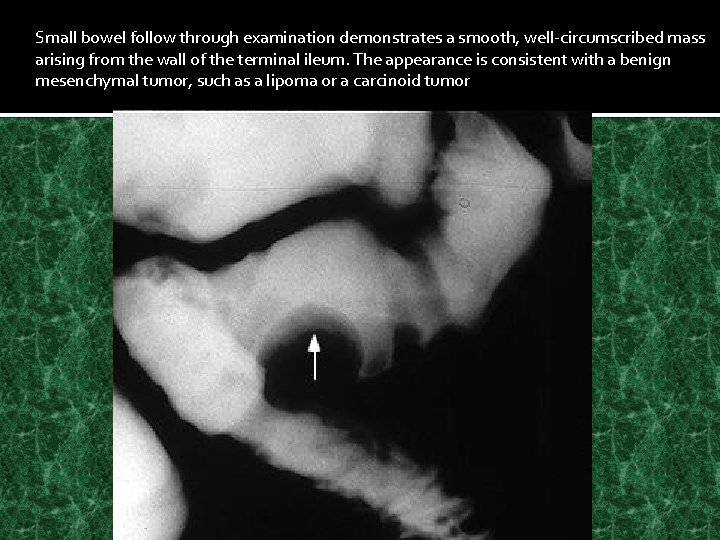

Small bowel follow through examination demonstrates a smooth, well-circumscribed mass arising from the wall of the terminal ileum. The appearance is consistent with a benign mesenchymal tumor, such as a lipoma or a carcinoid tumor